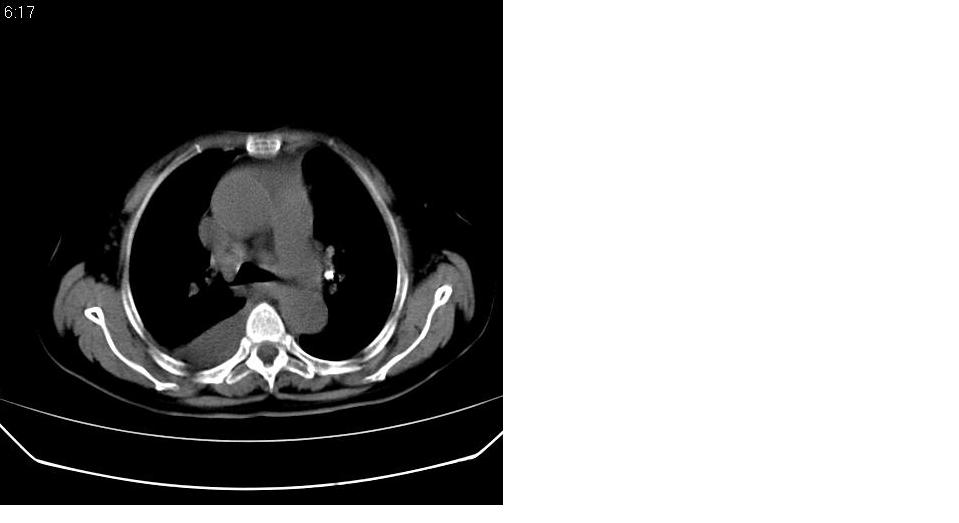

以下是引用haha215315在2007-7-11 9:10:00的发言:[br]全心衰所致心包积液、胸腔积液、肺水肿。

以下是引用liaizhi在2007-7-11 15:41:00的发言:[br]两肺纹理增粗,肺门影增大,气管支气管通畅。升主动脉壁及冠状动脉壁钙化。左房左室稍扩大。心包积液,胸腔积液。考虑冠心病并心功能不全,肺水肿,胸腔积液。